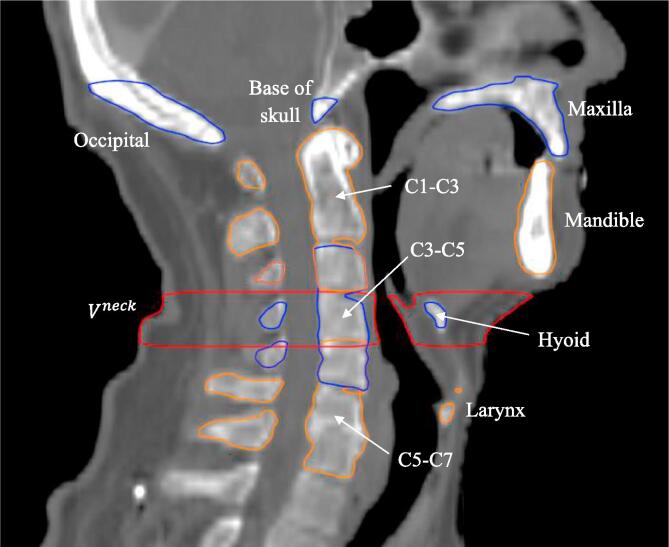

Nine bony anatomy (BA) structures were delineated on each patient’s computed tomography for treatment planning (pCT) scan: C1-C3, C3-C5, C5-C7, mandible, maxilla, base of skull, hyoid, occipital and larynx. A pre-defined neck volume was defined as all tissue within the volume bounded by axial planes at the base of C3 at the anterior cortical boundary and base of C4 at the anterior cortical boundary (Fig. 1). The original parotid gland (PG) contours were reviewed by a radiation oncologist and corrected where necessary to minimize the uncertainty of the DIR results.

Fig. 1.

Definition of bony anatomy (BA) structures and neck volume in the central sagittal plane. The superior end of the occipital bone contour was defined as to just include the external occipital protuberance.